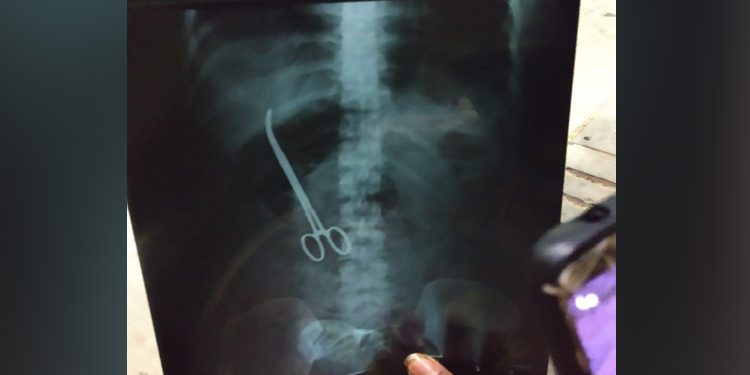

Hyderabad: In a shocking incident, doctors at Nizam’s Institute of Medical Sciences (NIMS) here, left artery forceps in a patient’s abdomen during a surgery.

This negligence by the doctors at the government-run super-speciality hospital came to light Saturday when an X-ray revealed that a pair of forceps was embedded in the stomach of Maheshwari Chowdary.

The 33-year-old had undergone a surgery for hernia November 2 last year. But even after the surgery she complained of severe abdominal pain and an X-ray report revealed that surgeons had accidentally left the surgery tool in her stomach.

The woman is now admitted for another surgery to remove the forceps.